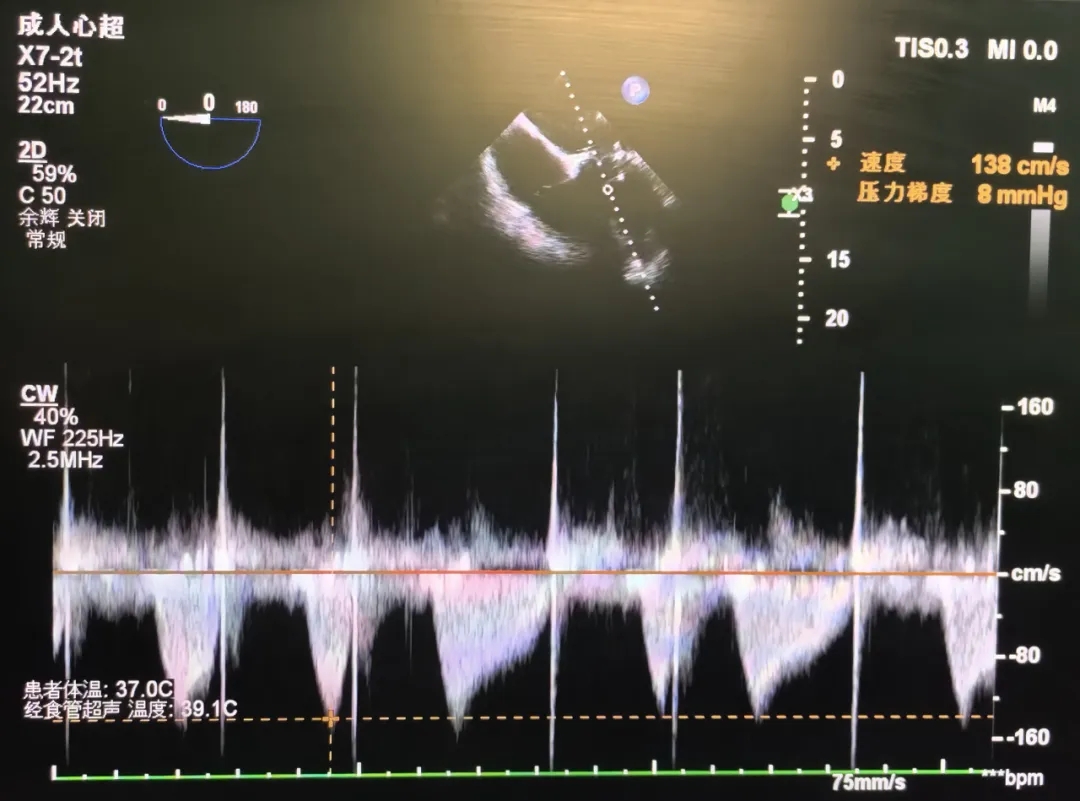

术后超声

手术圆满成功,即刻效果显著!

-

峰值流速:2.90m/s→1.28m/s

峰值压差:34mmHg→8mmHg

瓣周未见明显反流